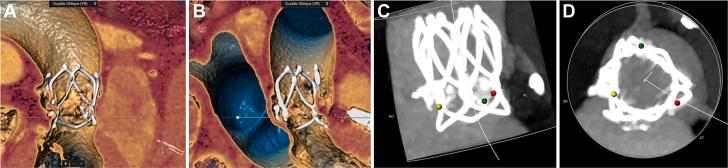

The indication for transcatheter aortic valve replacement to younger patients remains controversial. Here, we report a successful implantation of the first polymeric transcatheter aortic valve replacement device in a patient with severe calcific aortic stenosis. Compared with conventional valves, the novel valve has better durability, larger orifice area, and better morphological adaptability. ().

对于年轻患者进行经导管主动脉瓣置换术的适应症仍存在争议。在此,我们报告了首例聚合物经导管主动脉瓣置换装置在一名重度钙化性主动脉瓣狭窄患者中的成功植入。与传统瓣膜相比,这种新型瓣膜具有更好的耐用性、更大的开口面积和更好的形态适应性。()